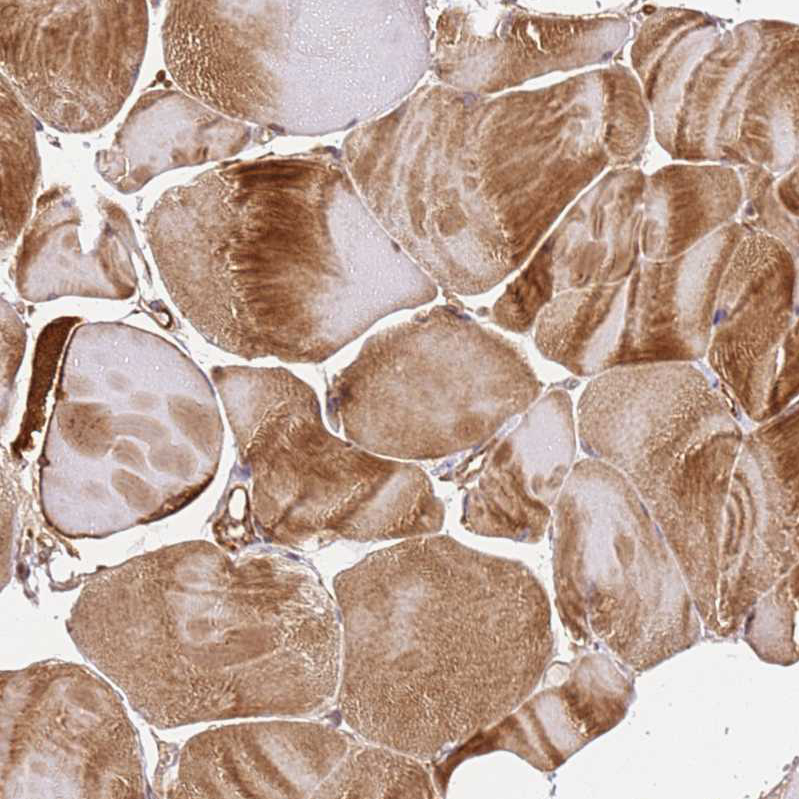

Immunohistochemical staining of human thyroid gland shows strong cytoplasmic positivity in glandular cells.